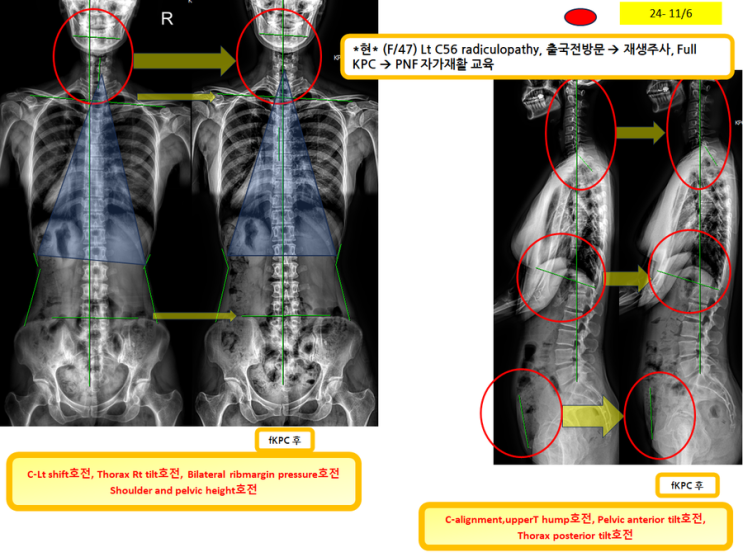

출국전에 full KPC받고 싶어 오신분!(녹는실KPC치료는 엑스레이 호전을 10분만에 확인)

출국전에 full KPC받고 싶어 오신분! (녹는실KPC치료는 엑스레이 호전을 10분만에 확인) full KPC...